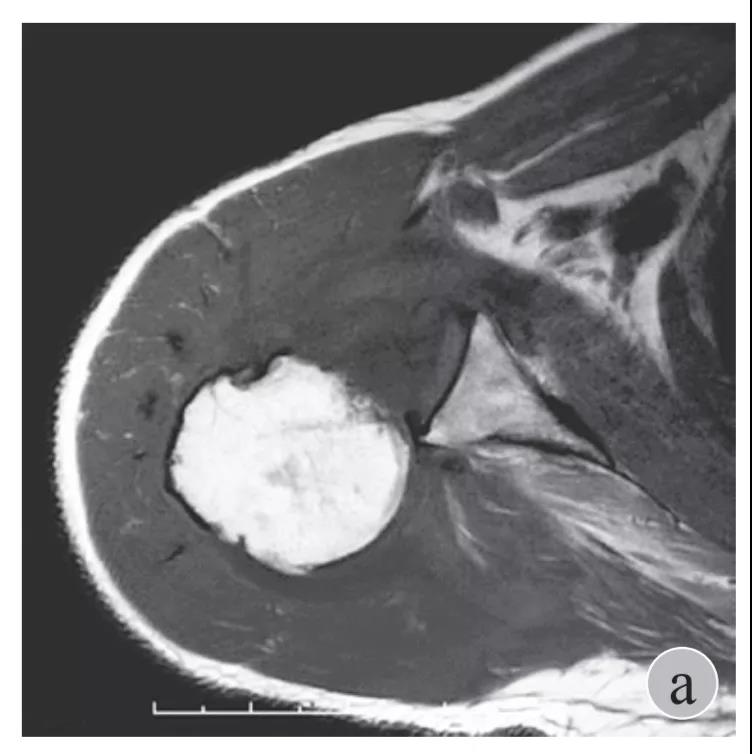

磁共振检查也完善了,还是报了个肩关节半脱位……影像科已经把坑挖好了……

就诊我院后完善CT,诊断明确——左肩关节后脱位:

予以手法复位后拍片复查显示“灯泡征”消失,复位成功。讨论:肩关节后脱位在临床较为少见,特别是影像科经验不足很容易漏报,所以我们临床医生一定要自己仔细阅片,同时要结合体查来进行诊断,防止漏诊。肩关节后脱位时体查也有明显特征:肩关节前方明显变平,喙突较平时明显凸起容易触及,而肩关节后方明显丰满,上臂一般处于内旋内收位,无法主动外旋外展。肩关节后脱位的手法复位相对于前脱位的复位来说也比较容易。患者一般可以取坐位,助手自患侧腋下环抱患者稳定患者躯体,术者一手拉患肢上臂稍牵引内旋,一手自后方推顶肱骨头一般可以复位,如果单纯推顶无法复位也可以术者两手握住伤肢缓慢外展并沿肱骨纵轴牵引,然后逐渐外旋上臂即可复位。整复完成后可以把持患肢作肩关节各个方向的小幅度被动活动,防止肩关节粘连,肩关节后脱位的固定方法与肩关节前脱位的固定方法不同,应将患肢置于上臂外展、后伸、外旋位固定,即外展30度、后伸30度和轻度外旋位,用外展支架固定3周后,循序渐进开始肩关节功能康复。